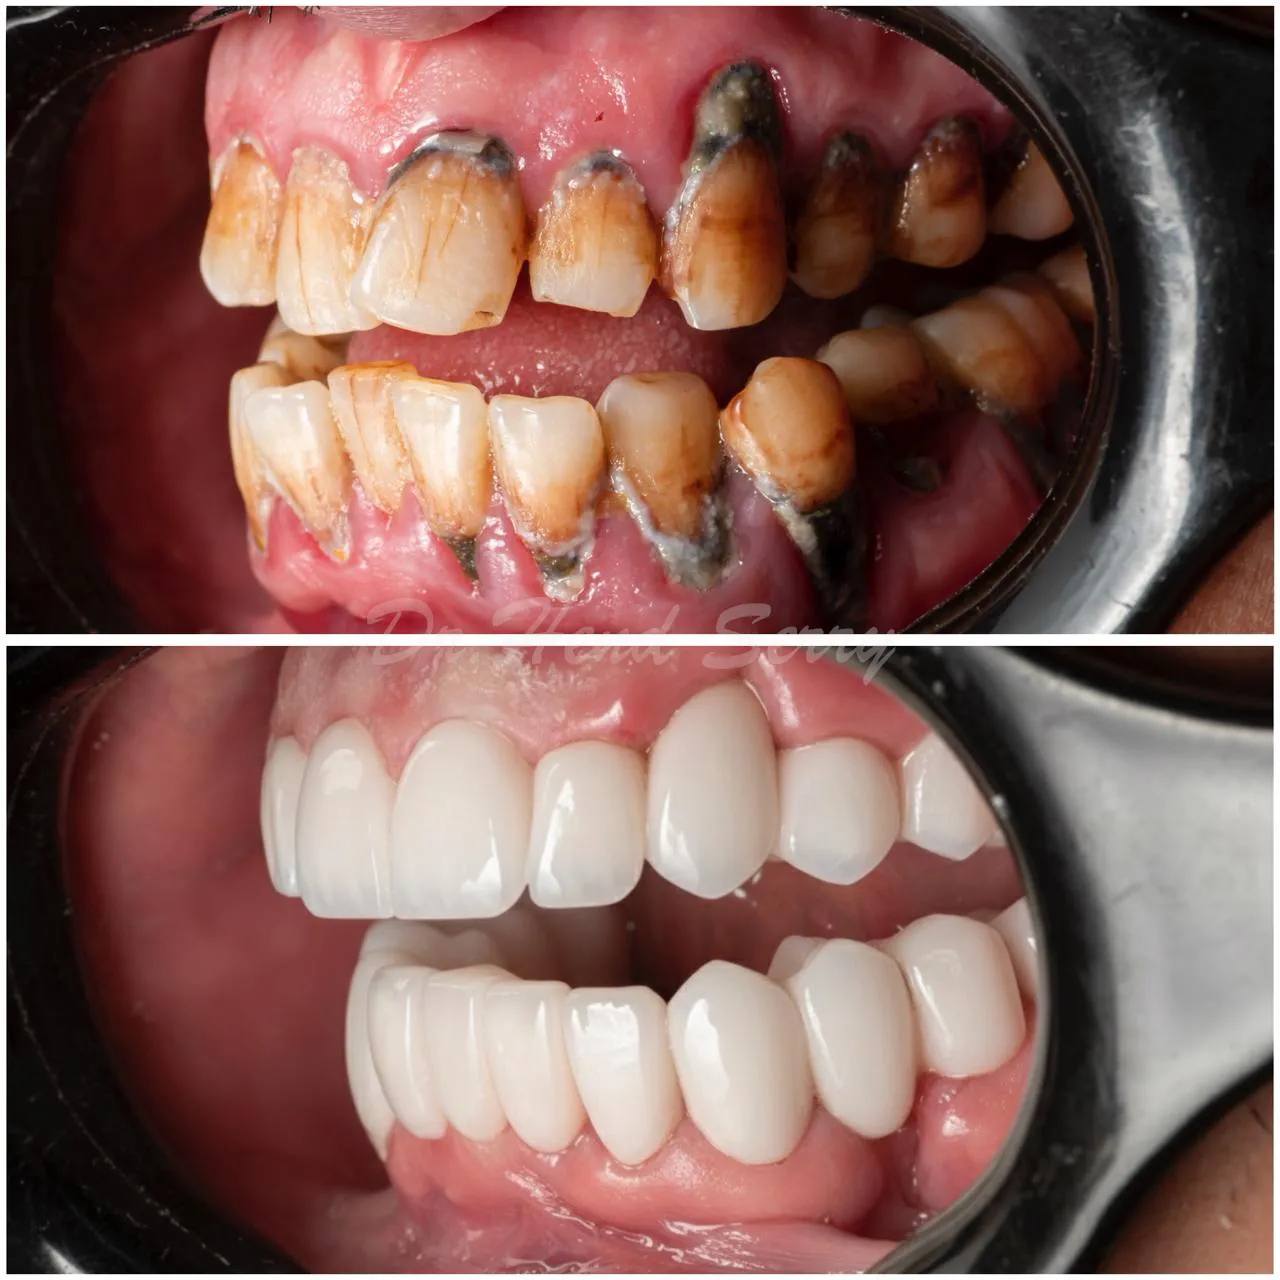

Full Mouth Reconstruction